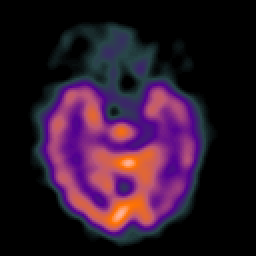

Alzheimer's disease: Perfusion SPECT -- Slice #17

[Home][Help][Clinical][Tour 1][Tour 2] Slice 17